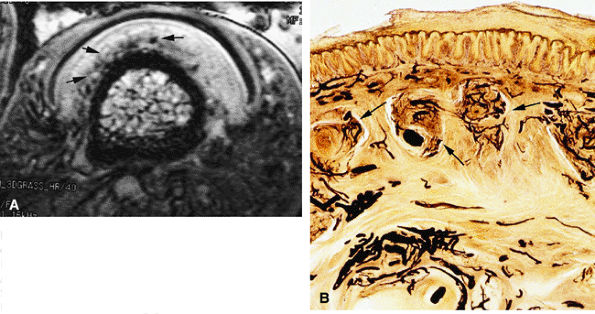

intensity. This heterogeneity is emphasized by the injection of gadolinium, which results in enhancement of the numerous glomus bodies of the nail bed (see Fig. 11.111; Fig. 11.112). Glomus bodies, which function as arteriovenous shunts, are highly concentrated in the fingertips, particularly beneath the nail plate.128 Each glomus body is a tiny encapsulated oval organ 300 μm long. The nail beds of fingers and toes contain 93 to 501 glomus bodies per square centimeter.

FIGURE 11.111 ● Photomicrograph of axial slice of the nail bed area with hematoxylin and eosin stain. The longitudinal ridges of the nail bed epithelium interdigitate with nail bed fibrocollagen. NP, nail plate; NBE, nail bed epithelium; G, glomus body; NBC, nail bed corium; LR, longitudinal ridges; DP, distal phalanx.

FIGURE 11.112 ● Glomus bodies. (A) Axial post-contrast 3D gradient-echo image of the nail bed showing multiple round foci representing glomus bodies (arrows). (B) Photomicrograph with transparency using the Spalteholz technique, vascular injection with gelatinous India ink, axial slice showing glomus bodies (arrows).